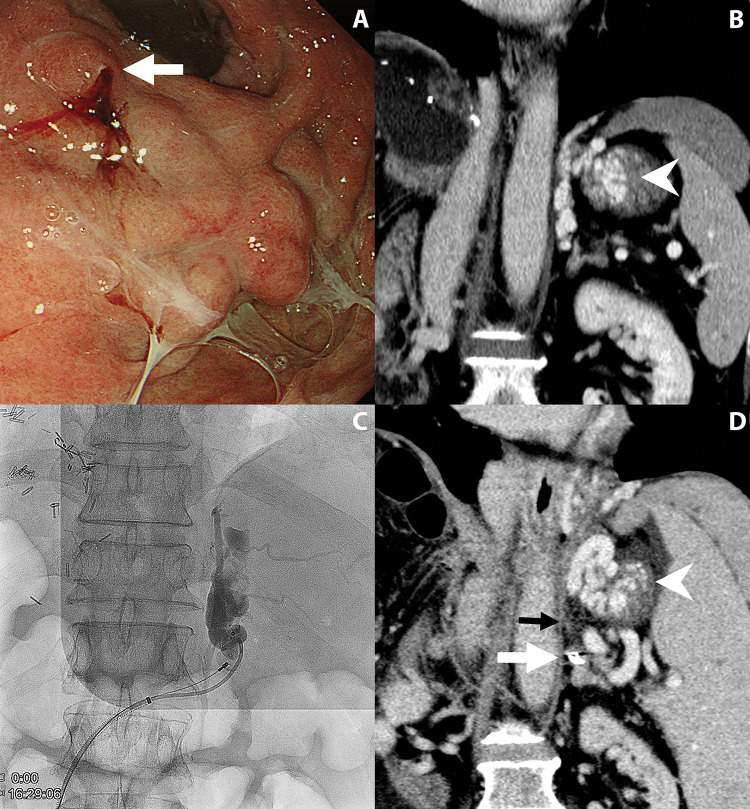

Purpose: To compare balloon-occluded retrograde transvenous obliteration (BRTO) using sodium tetradecyl sulfate and plug-assisted retrograde transvenous obliteration (PARTO), for treating symptomatic gastric varices. Materials and methods: A retrospective review of 51 consecutive patients (age: 63.7 ± 12.1 years; male: 72.6%) who underwent retrograde transvenous obliteration for gastric varices between June 2018 and July 2023 was conducted. Patients underwent BRTO (n = 26) or PARTO (n = 25) according to the preference of the attending interventional radiologist. The primary endpoint was complete obliteration. Secondary endpoints included technical and clinical success, post-embolization syndrome (PES), complications, and recurrent bleeding. Results: Technical success was achieved in 100% of BRTO group and 96% of PARTO group. Clinical success was achieved in all patients with technical success. One major complication in the PARTO group was due to shunt rupture during sheath passage, requiring fluid resuscitation and blood transfusion. In the BRTO group, there was a minor complication involving a balloon rupture, but the patient remained asymptomatic. PES was more frequent in the PARTO group (56%) compared to the BRTO group (23.1%) (p = 0.034). The median follow-up duration was 7 months. Complete obliteration rate was significantly higher in the BRTO group (100%) than in the PARTO group (80%) (p = 0.023). Recurrent bleeding occurred in one patient with remnant varix in the PARTO group. Conclusions: Both techniques achieved high technical and clinical success rates in the treatment of symptomatic gastric varices. However, BRTO demonstrated higher complete variceal obliteration and lower PES, suggesting a clinical advantage over PARTO.